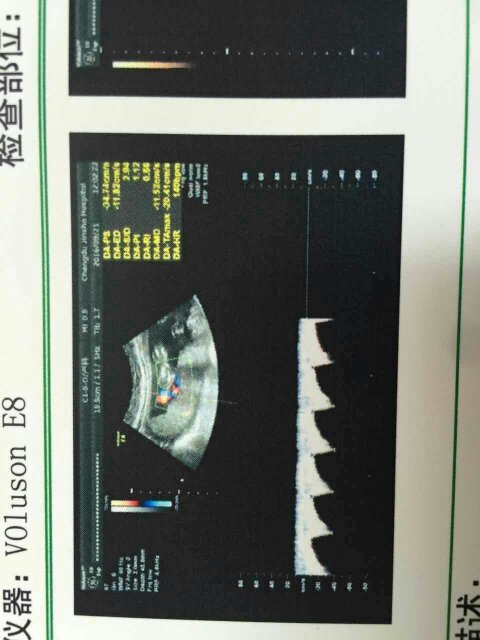

帮我看看吧,是男孩还是女孩,就是好奇绝对没有重男轻女的理想,怀孕刚好22周就做了四维!!

你好,我是bc师小洛 5年工作经验总结出的方法: 自己看吧! 望采纳! 首先数据不能超过8周,40多天是最合适的,孕囊都是圆柱状的,每个B超师做B超的时候,截面会截取的方位不一样,有的横截面,有的截取竖截面,如果是40*40*20,如果孕囊成等差数列,比如40*30*20,这样就是女孩,,有3个数据...的,是最好判断的,两个数据差不多,第三个数据比前两个小一倍,那肯定是儿子,如果成递减数据就是女儿。 ?还有一种情况就是第三个数据小很多的,比如40*38*10,像10比40和38小很多很多,这个也可能是女儿,但80%还是儿子。 ?有的数据最大数值不是在最前面,不要紧,把3个数据从大到小排好,自己看吧,比如:40*25*39,或者39*25*40,等等,这样都是儿子。 需要看男女的宝妈,可以WX我小洛lmyp666帮你看宝宝男女